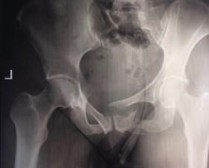

Рис. 1. КТ тазового кольца с 3Д реконструкцией пациента, до операции

Рис. 5. Рентгенограмма таза и КТ тазового кольца с 3Д реконструкцией пациента до операции